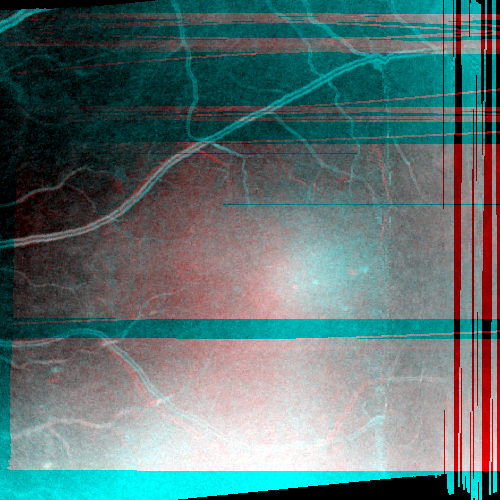

Images and estimated displacements are shown for a representative scan in Figureย 3. Tiny discontinuities prove absence of overregularization, and consistent transverse vibration indicates partial correction of ocular tremor. For quantitative analysis, we computed the median distance between the aligned A-scan displacements, and the fraction of displacements with a distance above 0.5 (problematic for supersampling) and 1 pixels (misalignments). The first and last 5% of B-scans were excluded, because they might not overlap with the orthogonal data, preventing registration. As the distributions are heavily skewed, we present box plots in Figureย 4. The three outliers in each direction in the right plot originate from the same subject, which is shown in supplementary Figureย 6. It is critical to note that the parameter density (B-scan rate 205 Hz) of the hermite splines is insufficient to fully correct ocular tremor (frequency up to 100 Hzย [16]). Therefore, this aperiodic, wave-like motion (amplitude 30โฒโฒ 1.6ย ยตm on the retinaย [16]) cannot be fully corrected, and neither is fully represented in the reproducibility error. In the transverse directions, this puts a lower accuracy limit on the evaluation scheme, but it is small compared to the pixel spacing (12ย ยตm). Using an Nvidia RTX 5000 GPU, the median and maximum runtime in the test set, excluding disk I/O which is irrelevant in clinical routine, was 8.6ย s and 31.3ย s. Tableย 1 compares average runtimes of various methods. Lastly, registration of individual B-scan repeats is demonstrated on a swept-source scanner in Figureย 5.